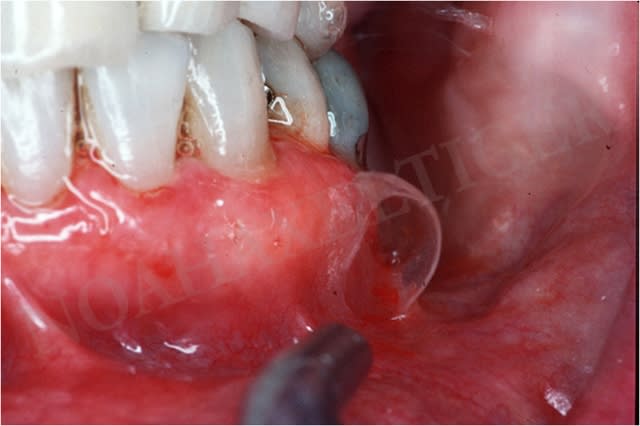

juste une photo d'un pemphigoïde

une bonne gingivite desquamative !!!!

doit faire mal ça...